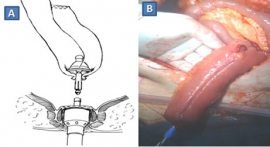

Πρόκειται για μαζική διάταση παχέος εντέρου απουσία μηχανικής απόφραξης, οδηγώντας σε σοβαρό ειλεό του παχέος εντέρου. Προκύπτει από δυσενέργεια του αυτόνομου νευρικού συστήματος. Αποτελεί διάγνωση αποκλεισμού και θα πρέπει να αποκλειστούν τα αίτια παραλυτικού ειλεού (που προσβάλλει λεπτό και παχύ έντερο) και τα αίτια απόφραξης του παχέος εντέρου. Αιτιολογία…